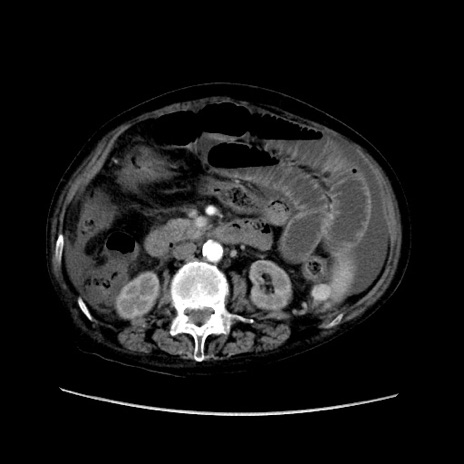

症例31(横断像)

【症例】80歳代 女性

【主訴】腹部膨満感

【現病歴】他院にて肝硬変にてフォロー中。1週間前から便秘、腹部膨満感、臍部腫瘤あり受診となる。

【既往歴】肝硬変

【身体所見】腹部膨隆あり、皮膚変化なし、疼痛なし。

【データ】WBC 4600、CRP 0.25